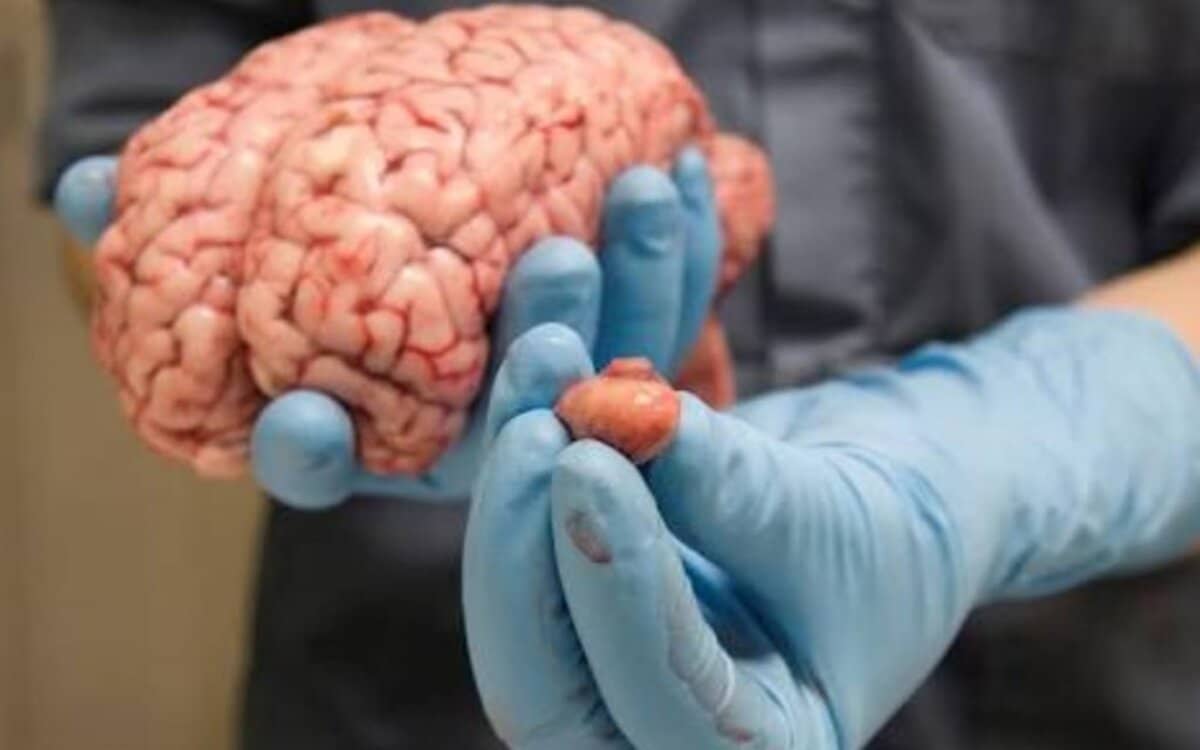

تقع الغدة النخامية في منطقة قاعدة الدماغ وراء الأنف، ولا يتجاوز حجمها حجم حبة البازيلاء، ولكن على الرغم من صغر حجمها فإن الغدة النخامية تُعد جزءًا أساسيًا من أجزاء الجهاز الصماوي، أي أنها المسؤولة عن إفراز الهرمونات التي تعمل بشكل منفرد، مثل هرمون النمو وهرمون البرولاكتين.

كما أن الغدة النخامية تقوم بإفراز عدد من الهرمونات التي تؤثر على الغدد الأخرى مثل الغدة الدرقية والغدة الكظرية والخصيتين والمبيضين، وعند الإصابة بأورام الغدة النخامية فإن الغدة النخامية تنتج مستويات أقل من الهرمونات مما يؤثر على الصحة والجسم.

وتحدث أورام الغدة النخامية في حالة نمو خلايا بشكل غير طبيعي في الغدة النخامية، مما يؤدي إلى إفراز الكثير من الهرمونات التي لا يحتاجها الجسم، أو أو يضغط الورم على الغدة النخامية ويتسبب في إنتاج مستويات أقل من الهرمونات التي يحتاجها الجسم، وفي كلتا الحالتين ينتج عنها مشاكل صحية عديدة، لذلك لابد من التخلص من هذا الورم إما بالجراحة أو بالعلاجات الأخرى.

وقد تسبب الأورام الكبيرة في الحجم في الغدة النخامية مشاكل عديدة نظرًا لحجمها، كالصداع أو مشاكل عدة في النظر، ولكن غالبية أورام الغدة النخامية هي أورام حميدة غير سرطانية، أي أنها تبقى في الغدة النخامية أو الأنسجة المحيطة ولا تنتشر إلى أجزاء أخرى من الجسم.